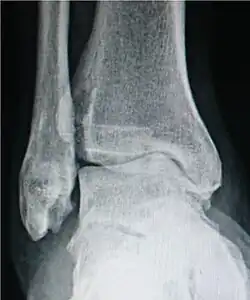

Ankle osteoarthritis.

• For the ankle, the Kellgren–Lawrence scale, as described for the hip, has been recommended.[16] The distances between the bones in the ankle are normally as follows:[17]

• Talus - medial malleolus: 1.70 ± 0.13 mm

• Talus - tibial plafond: 2.04 ± 0.29 mm

• Talus - lateral malleolus: 2.13 ± 0.20 mm